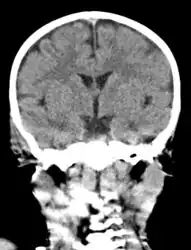

The diagnosis of mastoiditis is clinical—based on the medical history and physical examination. Imaging studies provide additional information; The standard method of diagnosis is via MRI scan although a CT scan is a common alternative as it gives a clearer and more useful image to see how close the damage may have gotten to the brain and facial nerves. Planar (2-D) X-rays are not as useful. If there is drainage, it is often sent for culture, although this will often be negative if the patient has begun taking antibiotics. Exploratory surgery is often used as a last resort method of diagnosis to see the mastoid and surrounding areas.[7][8]